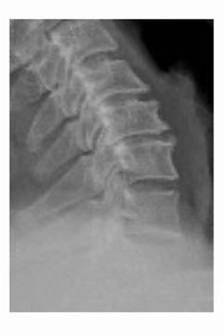

术前 图片4

术前 图片5

术前 图片6